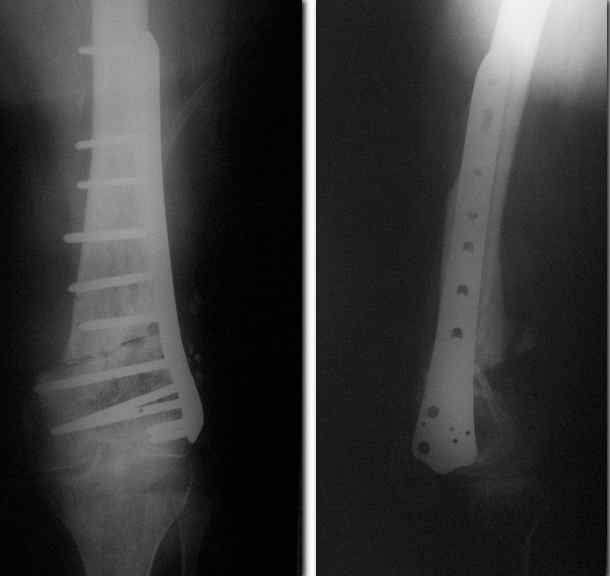

Выглядит красиво. А движения в колене какие были на столе?

Была контрактура и спаянный с суставной поверхностью надколенник. Сделали до синтеза редрессацию. Достигли почти полного объема движений.